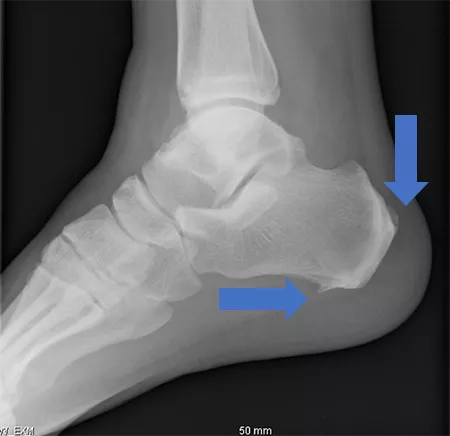

写真3 単純X線踵骨側面像

case001_03_rev.png

踵骨のアキレス腱および足底腱膜付着部に靭帯骨棘形成あり